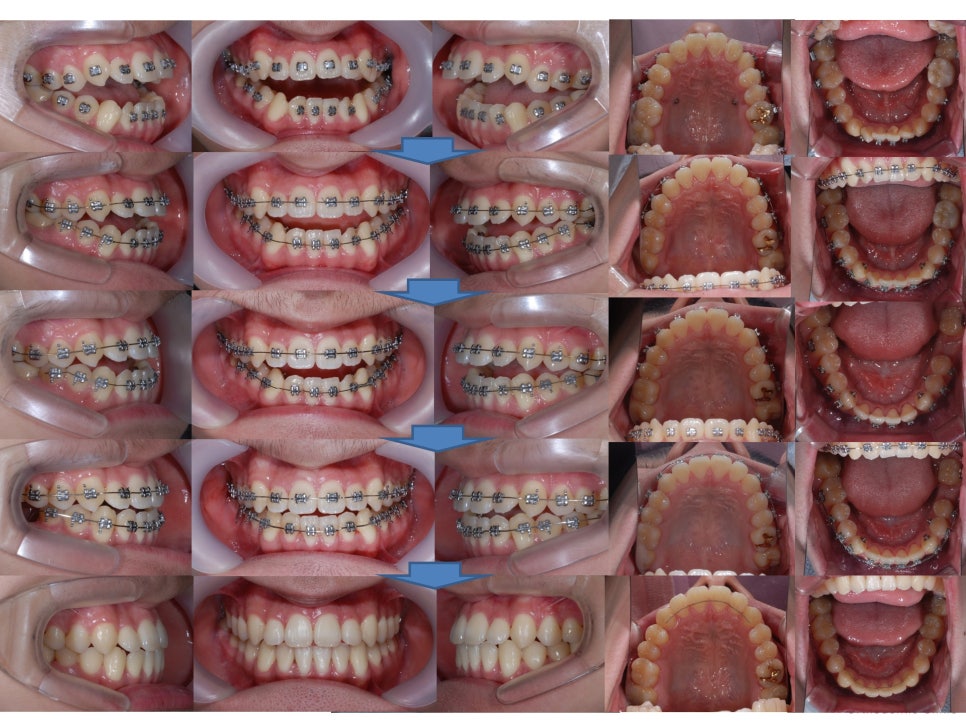

¾È¸éºñ´ëĪ Ä¡¾Æ±³Á¤ + °³¹æ±³ÇÕ Ä¡¾Æ±³Á¤

°³¹æ±³ÇÕÀÌ ¸¹ÀÌ °³¼±µÈ °ÍÀ» º¼ ¼ö ÀÖ½À´Ï´Ù.

¾È¸éºñ´ëĪ Ä¡¾Æ±³Á¤+

°³¹æ±³ÇÕ Ä¡¾Æ±³Á¤ÀÌ

Àß ¸¶¹«¸®µÈ °ÍÀ» º¼ ¼ö ÀÖ½À´Ï´Ù.

Àü¹ÝÀûÀÎ

ºñ¼ö¼ú ¾È¸éºñ´ëĪ Ä¡¾Æ±³Á¤

ºñ¼ö¼ú °³¹æ±³ÇÕ Ä¡¾Æ±³Á¤

Ä¡·á°úÁ¤ÀÔ´Ï´Ù.

ÀüÈÄÀÇ ¾ó±¼º¯È­ ÀÔ´Ï´Ù.